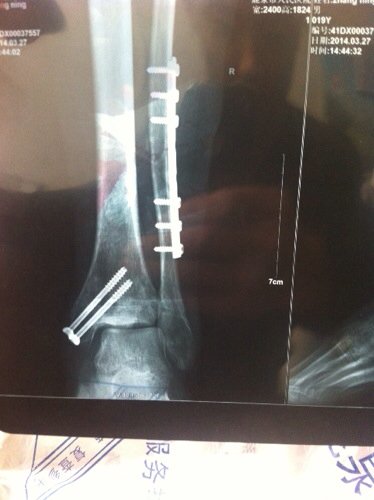

这种骨折会留下后遗症吗 现在术后五个月脚走起来还是疼还是肿弯曲度很小怎么办急 点击展开 匿名用户 2014-04-23 18:07 为您推荐: 其他回答 病情分析: 您好,对于您说的情况看骨折对位对线是很好的,手术是很成功的。 指导意见: 吃药骨折愈合的话,一般是不会存留什么不良后果的。 匿名用户 2014-04-24 15:26 相关问题 小孩右大腿骨骨折后,明显向前弯曲、成角会有后遗症吗?-骨折 脚脖子骨折五个月了还肿 可不可以打消炎针啊! 老妈右侧宽臼骨折八个月、走路脚为啥肿